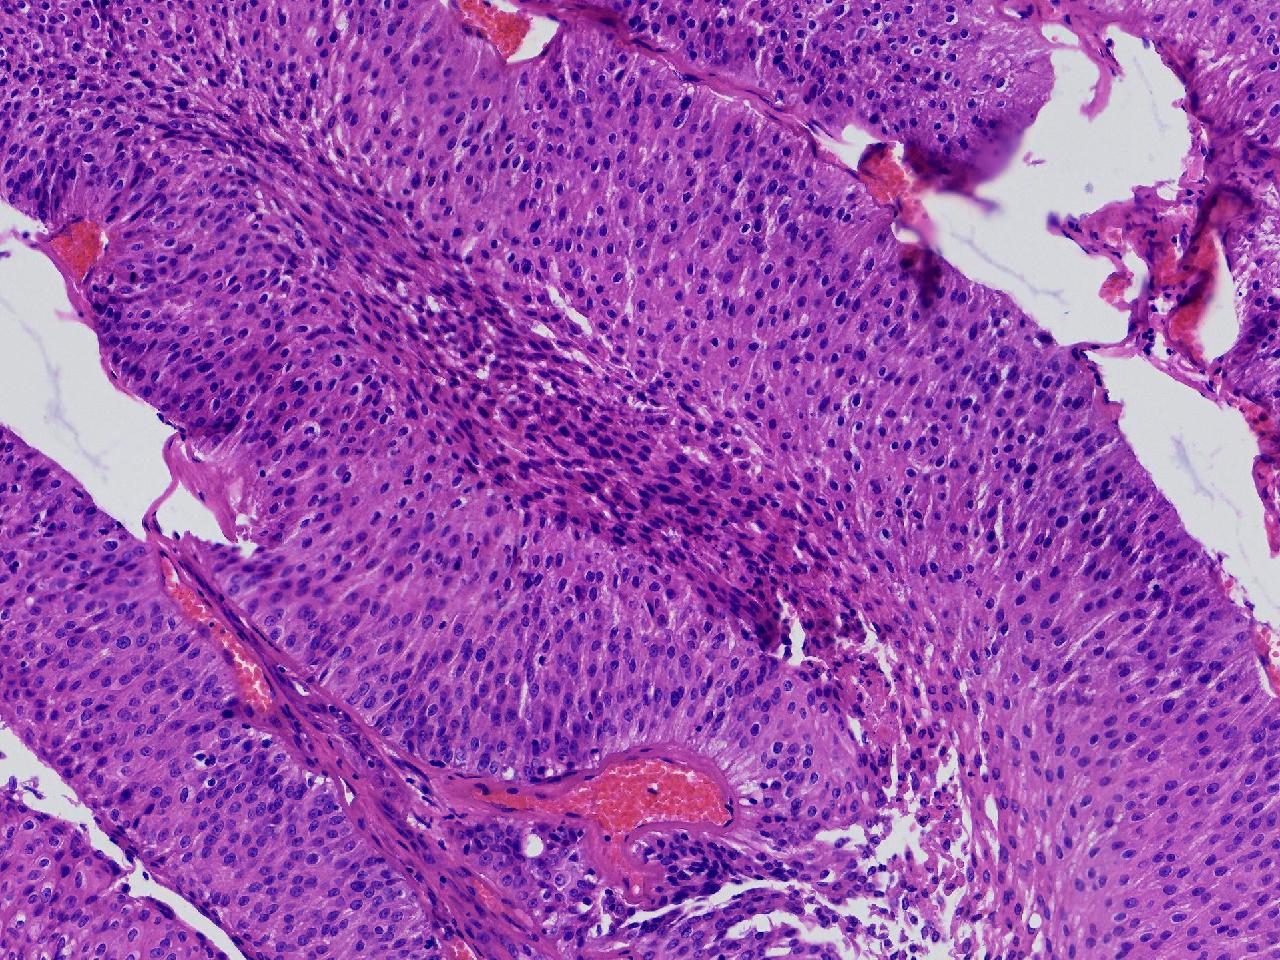

男,79岁,膀胱肿物。

膀胱肿物

灰白色不整形软组织多块,2X1X1厘米。

考虑:乳头状尿路上皮癌

考虑低级别,非浸润。

乳头状尿路上皮癌,低级别。

这几张图片上没有看到明确的浸润。